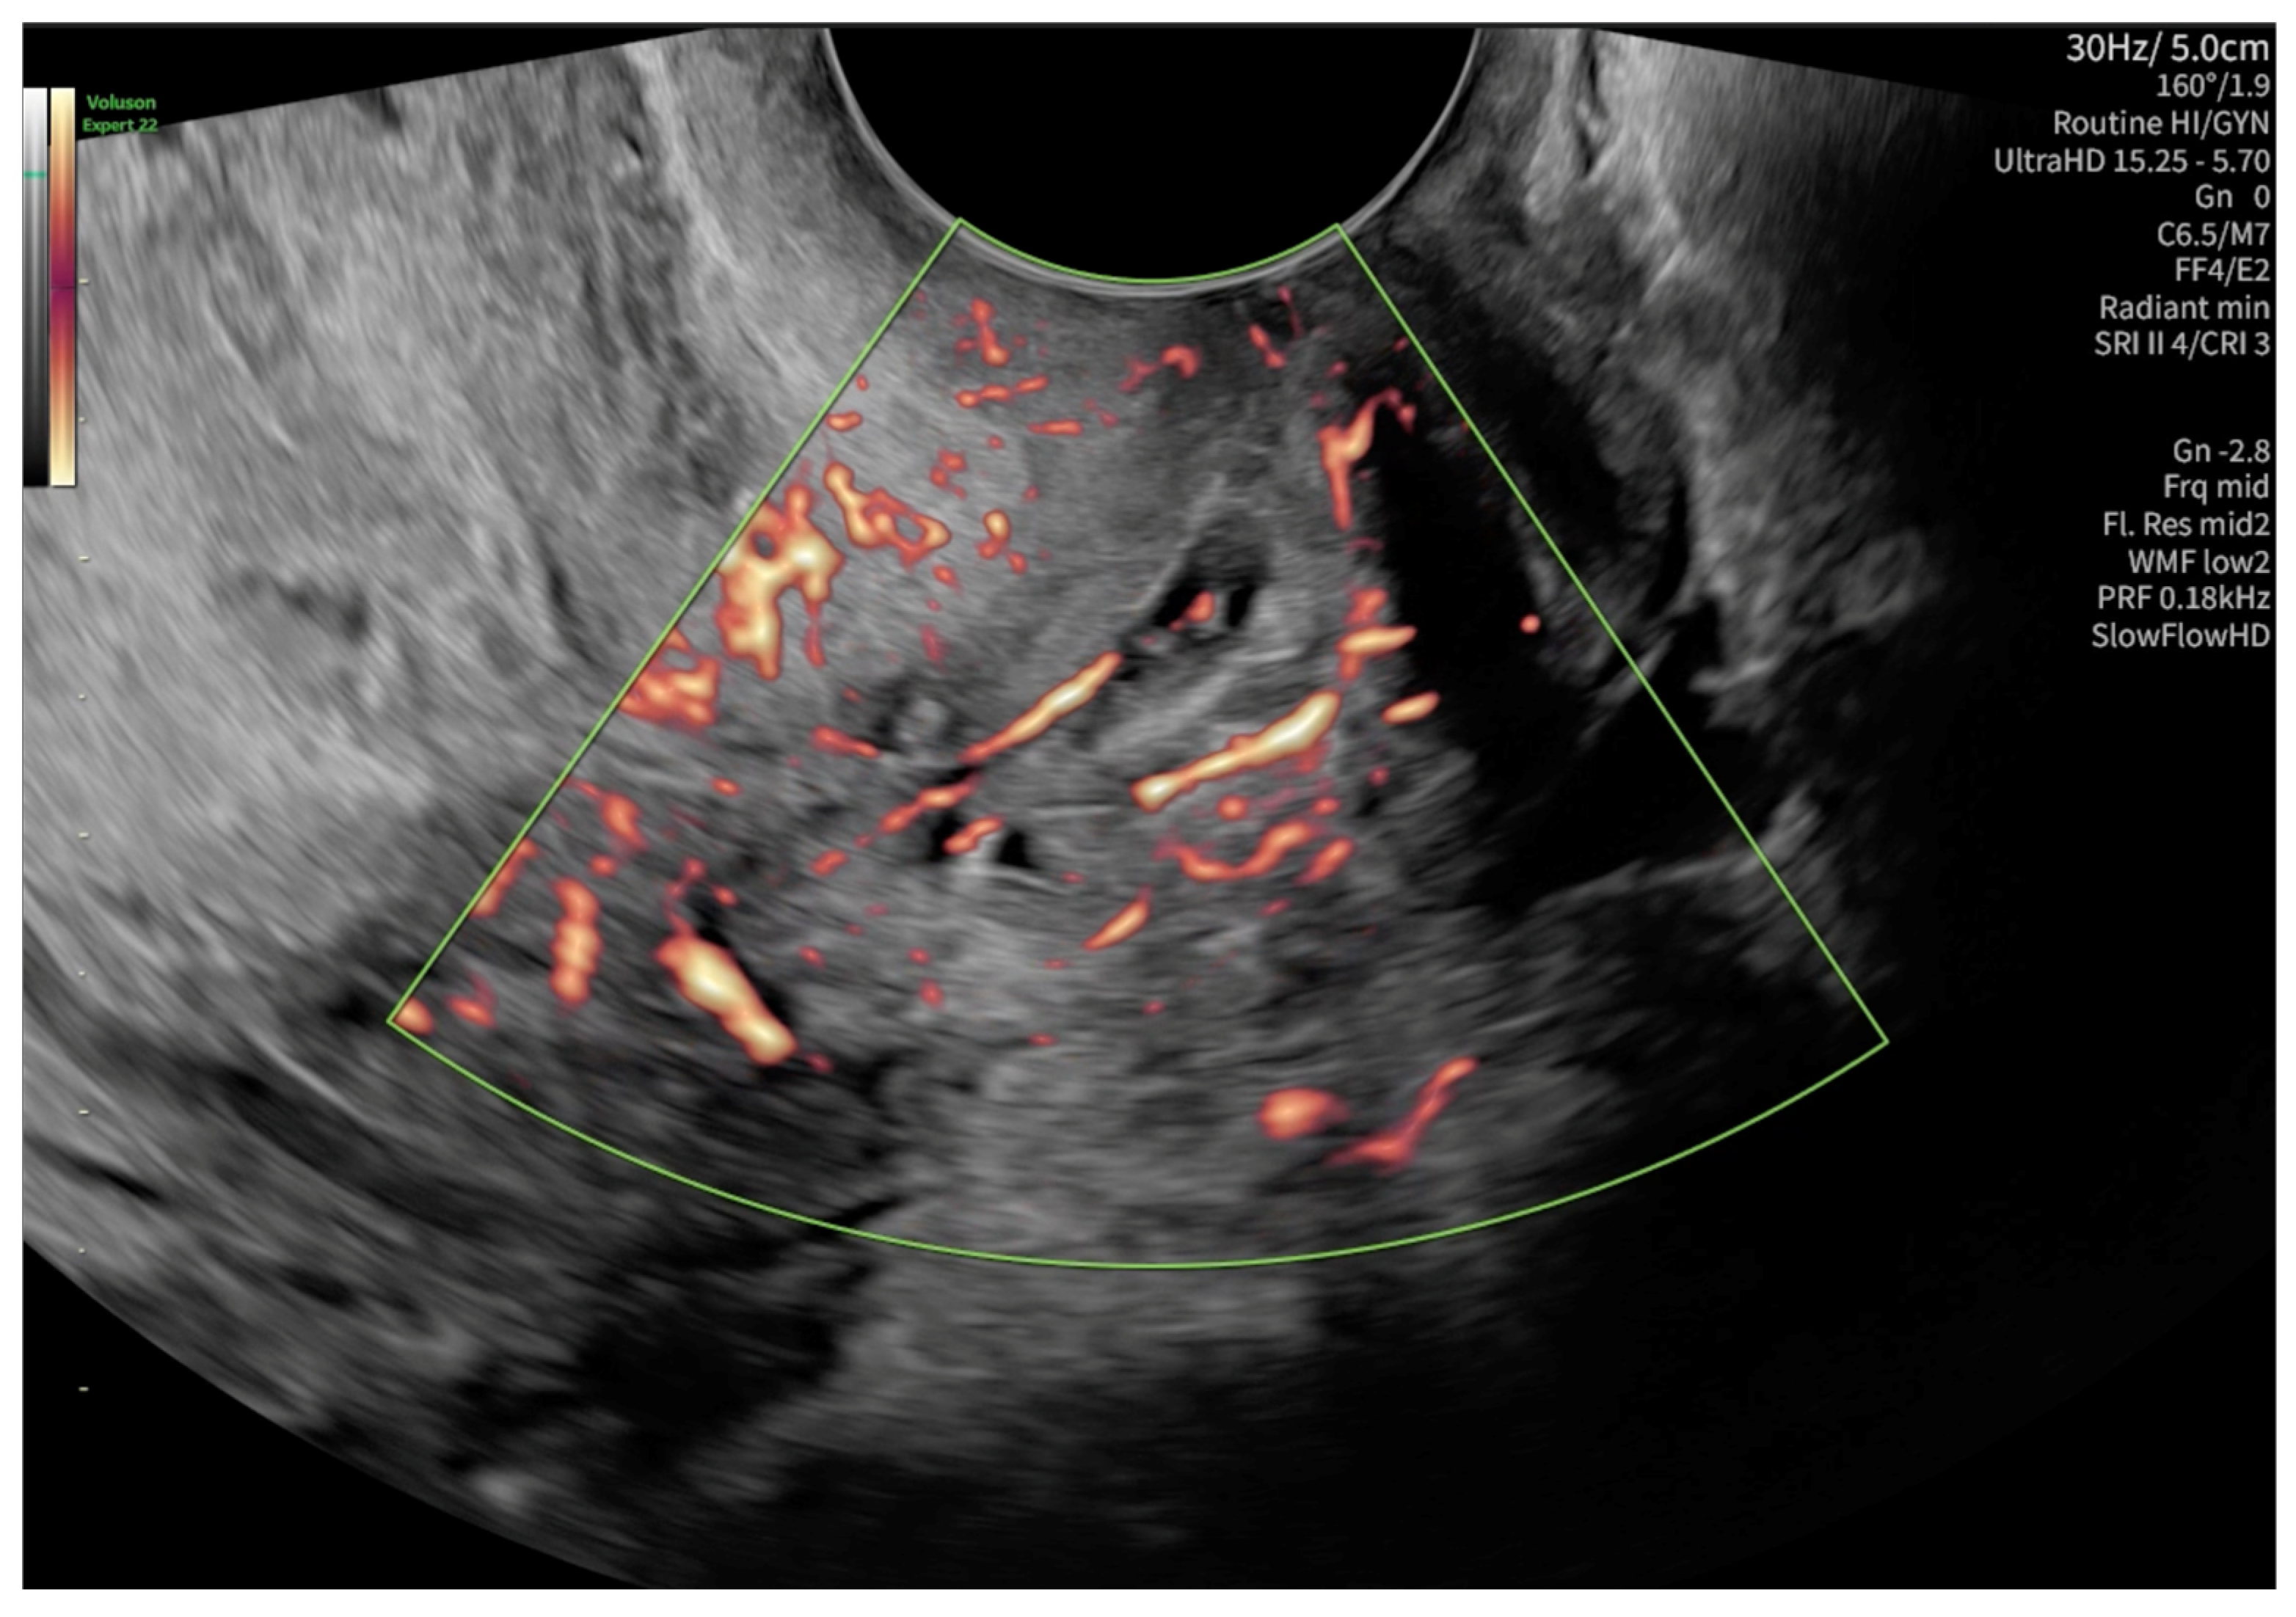

2. Case Presentation